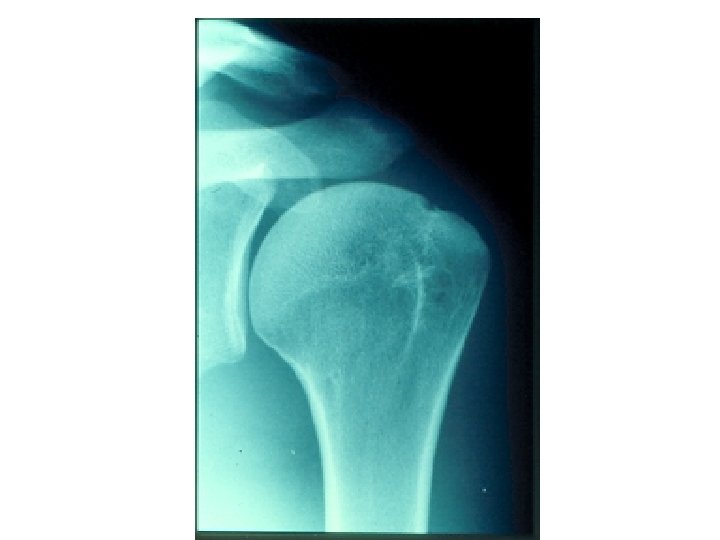

SEMIOLOGIE DE L’EPAULE IV – DIAGNOSTIC ETIOLOGIQUE A – Atteintes périarticulaires B – Rétraction

SEMIOLOGIE DE L’EPAULE IV – DIAGNOSTIC ETIOLOGIQUE A – Atteintes périarticulaires B – Rétraction capsulaire de l’épaule (épaule gelée – algodystrophie) C – Arthroses de l’épaule D – Arthrites – rhumatismale (contexte) – infectieuse +++